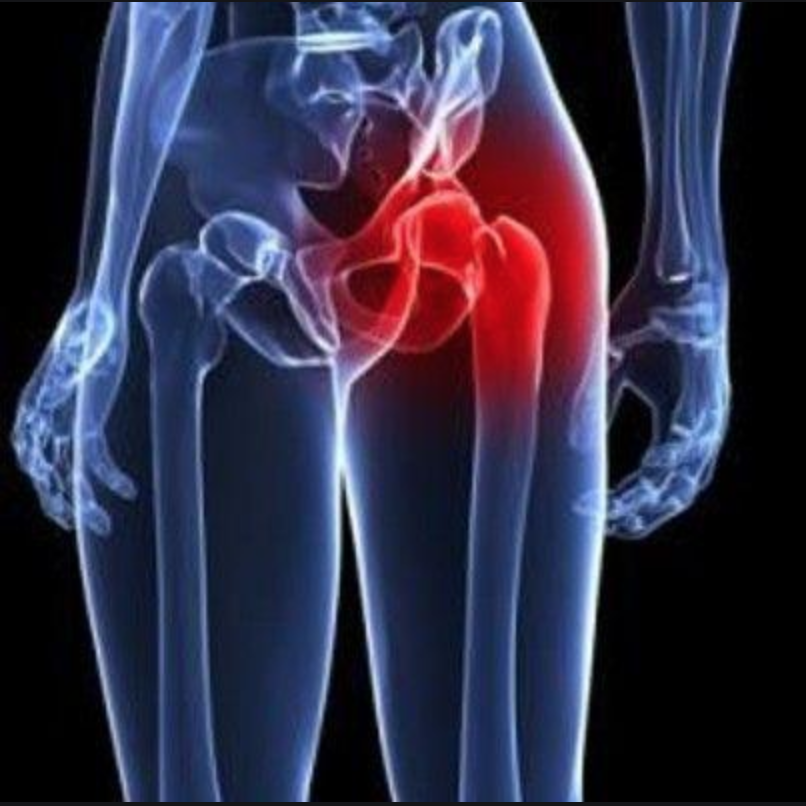

Боль в малом тазу у женщин: Причины и подходы к лечению